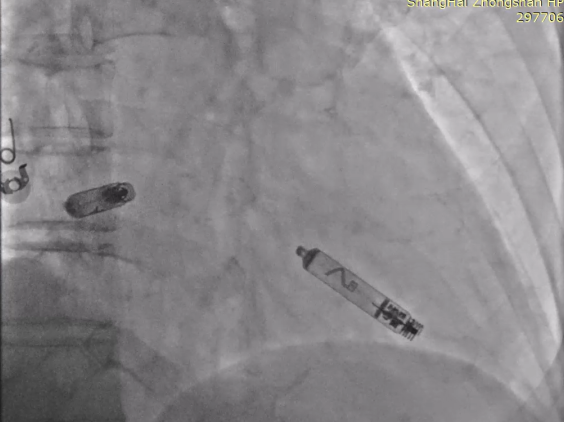

手术继续,通过猪尾造影提示植入目标位点后,优先植入心室VR,作为备用起搏,随后植入心房AR,标准流程释放无导线起搏器后,配对Aveir™ AR及VR,程控为DDD模式。

最终植入影像:

RAO30

LAO30